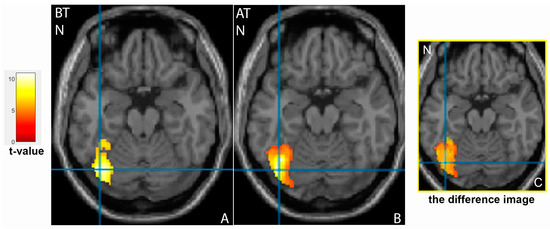

3.2. Comparison of Brain Activation Patterns in Patients before and after Treatment

| Cluster Location | Emotion | Extent | t-Value | p (FWE Corrected) | MNI Coordinates |

|---|---|---|---|---|---|

| Patients group after therapy | |||||

| Frontal cortex | |||||

| Right inferior frontal gyrus | N | 1390 | 10.97 | <0.001 | 38;4;28 |

| Right middle frontal gyrus | N- | 386 | 5.51 | 0.008 | 46;30;26 |

| Occipital cortex | |||||

| Left fusiform gyrus, BA37 | N | 1532 | 6.48 | <0.001 | −40;−68;−20 |

| Right fusiform gyrus, BA37 | N | 1861 | 7.44 | <0.001 | 44;−58;−24 |

| Temporal cortex | |||||

| Left superior temporal gyrus, BA22 | N- | 420 | 5.94 | 0.005 | −48;12;−4 |